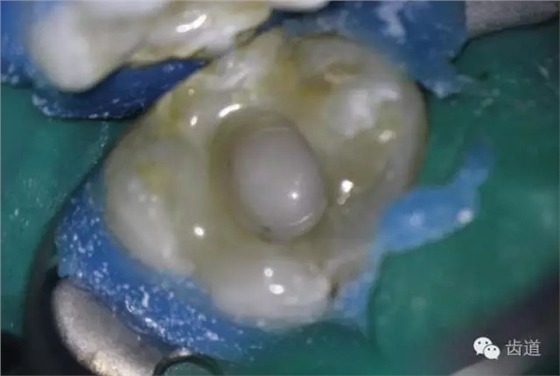

10. 術(shù)后即刻口內(nèi)照片

檢查:術(shù)后半年回訪,37牙體及合面嵌體未見缺損及裂紋,邊緣密合,未探及繼發(fā)齲,探痛-,叩痛-,松動(dòng)-,冷水刺激痛-,未探及牙周袋及附著喪失,牙齦無紅腫,X線片檢查示根尖周膜連續(xù)性恢復(fù),根尖周透射影消失。

1. 術(shù)后半年口內(nèi)照片